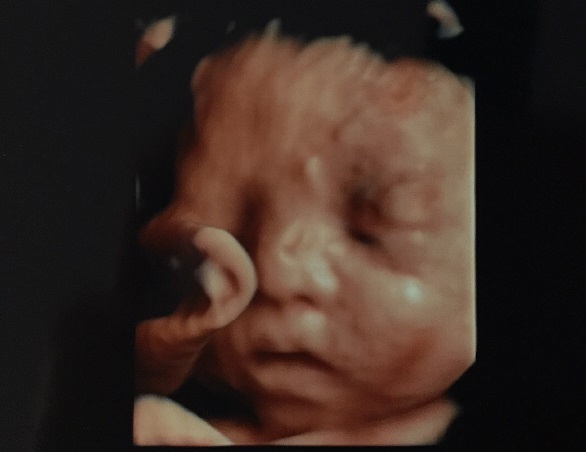

29週0日(29w0d・男の子)|yuiiing52 さん(31歳)

エコー写真撮影時のエピソード:

エコー写真はいつ見ても、どれが顔なのかどれが足とか全然分かりませんでした。3Dと4Dを同じに日に撮って、4Dの方が分かりにくくて、旦那様は全く分かってなくて、帰って録画したのを見て説明しました。

この3Dが1番きれいに撮れて、でも先生はボッコボコとエコーのやつでグイグイ押してたので、こんな押して大丈夫と不安でしたが、いい写真が撮れました。